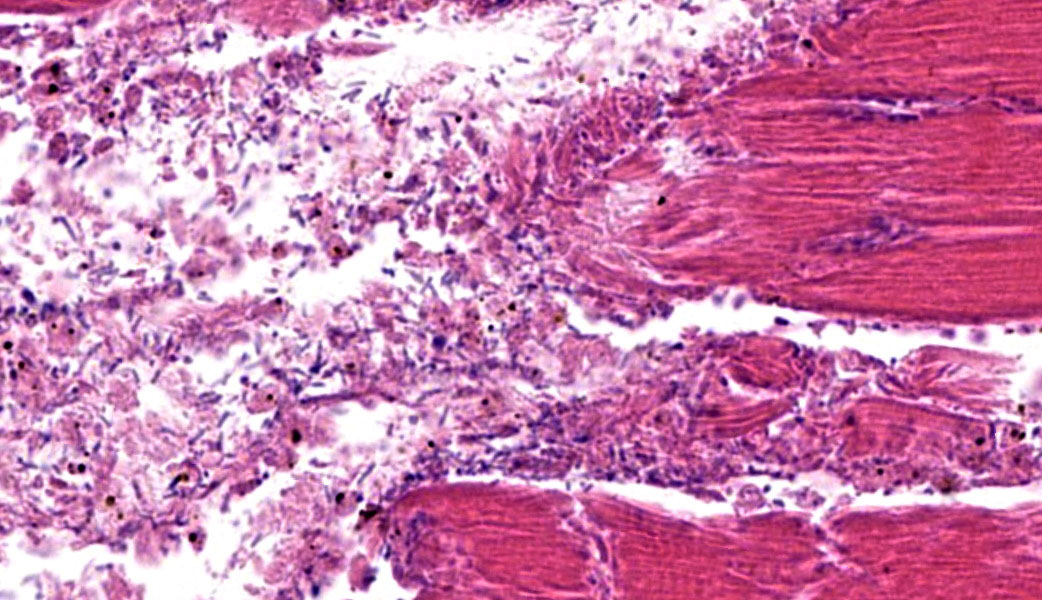

Microscopic Description:

The grossly affected skeletal muscle is necrotic with swollen, hypereosinophilic to pale staining myofibers that have lost their cross striations. The sarcoplasm of small numbers of myofibers is fragmented and replaced by eosinophilic flocculent material. The interstitium is emphysematous and contains small amounts of hemorrhage and edema that separate individual myofibers and the endomysium. There are also numerous large bacilli and a few perivascular to random multifocal infiltrates of small numbers of degenerate neutrophils in the interstitium. There are small numbers of arterioles and venules with necrosis of the vascular wall.

Skeletal muscle: Acute necrosis with emphysema, hemorrhage, mild suppurative myositis and numerous intralesional bacilli; etiology, Clostridium novyi.

Clostridial myonecrosis can develop in multiple species, but is most common in ruminants, horses, and swine.3 In all species, skeletal muscle necrosis in the primary lesion. The muscle necrosis is accompanied by edema, hemorrhage, and often emphysema. The hemorrhage and lysis of erythrocytes cause the affected skeletal muscle to be dark red to black.

The necrotic skeletal muscle often has a rancid odor. The microscopic lesions mirror the gross lesions. The primary microscopic lesion is necrotic myofibers that are separated by edema, hemorrhage and lysed erythrocytes. The skeletal muscle may be emphysematous. There typically are very few neutrophils within the lesion. The number of bacteria in the lesion varies widely with the lesions in some animals containing large numbers of bacteria with the lesions in other animals containing small numbers of bacteria. Most lesions have small numbers of bacteria. Fragmentation of the necrotic myofibers in the deeper aspects of the lesions may be present. The affected animals die quickly usually within twenty-four hours if not treated. The histotoxic clostridia spread quickly throughout the carcass postmortem resulting in rapid decomposition. Because these bacteria spread quickly throughout the carcass postmortem, one has to be careful in interpreting positive identification of histotoxic clostridia within muscle lesions as the Clostridium species identified may be a postmortem contaminant rather than the cause of the muscle necrosis.